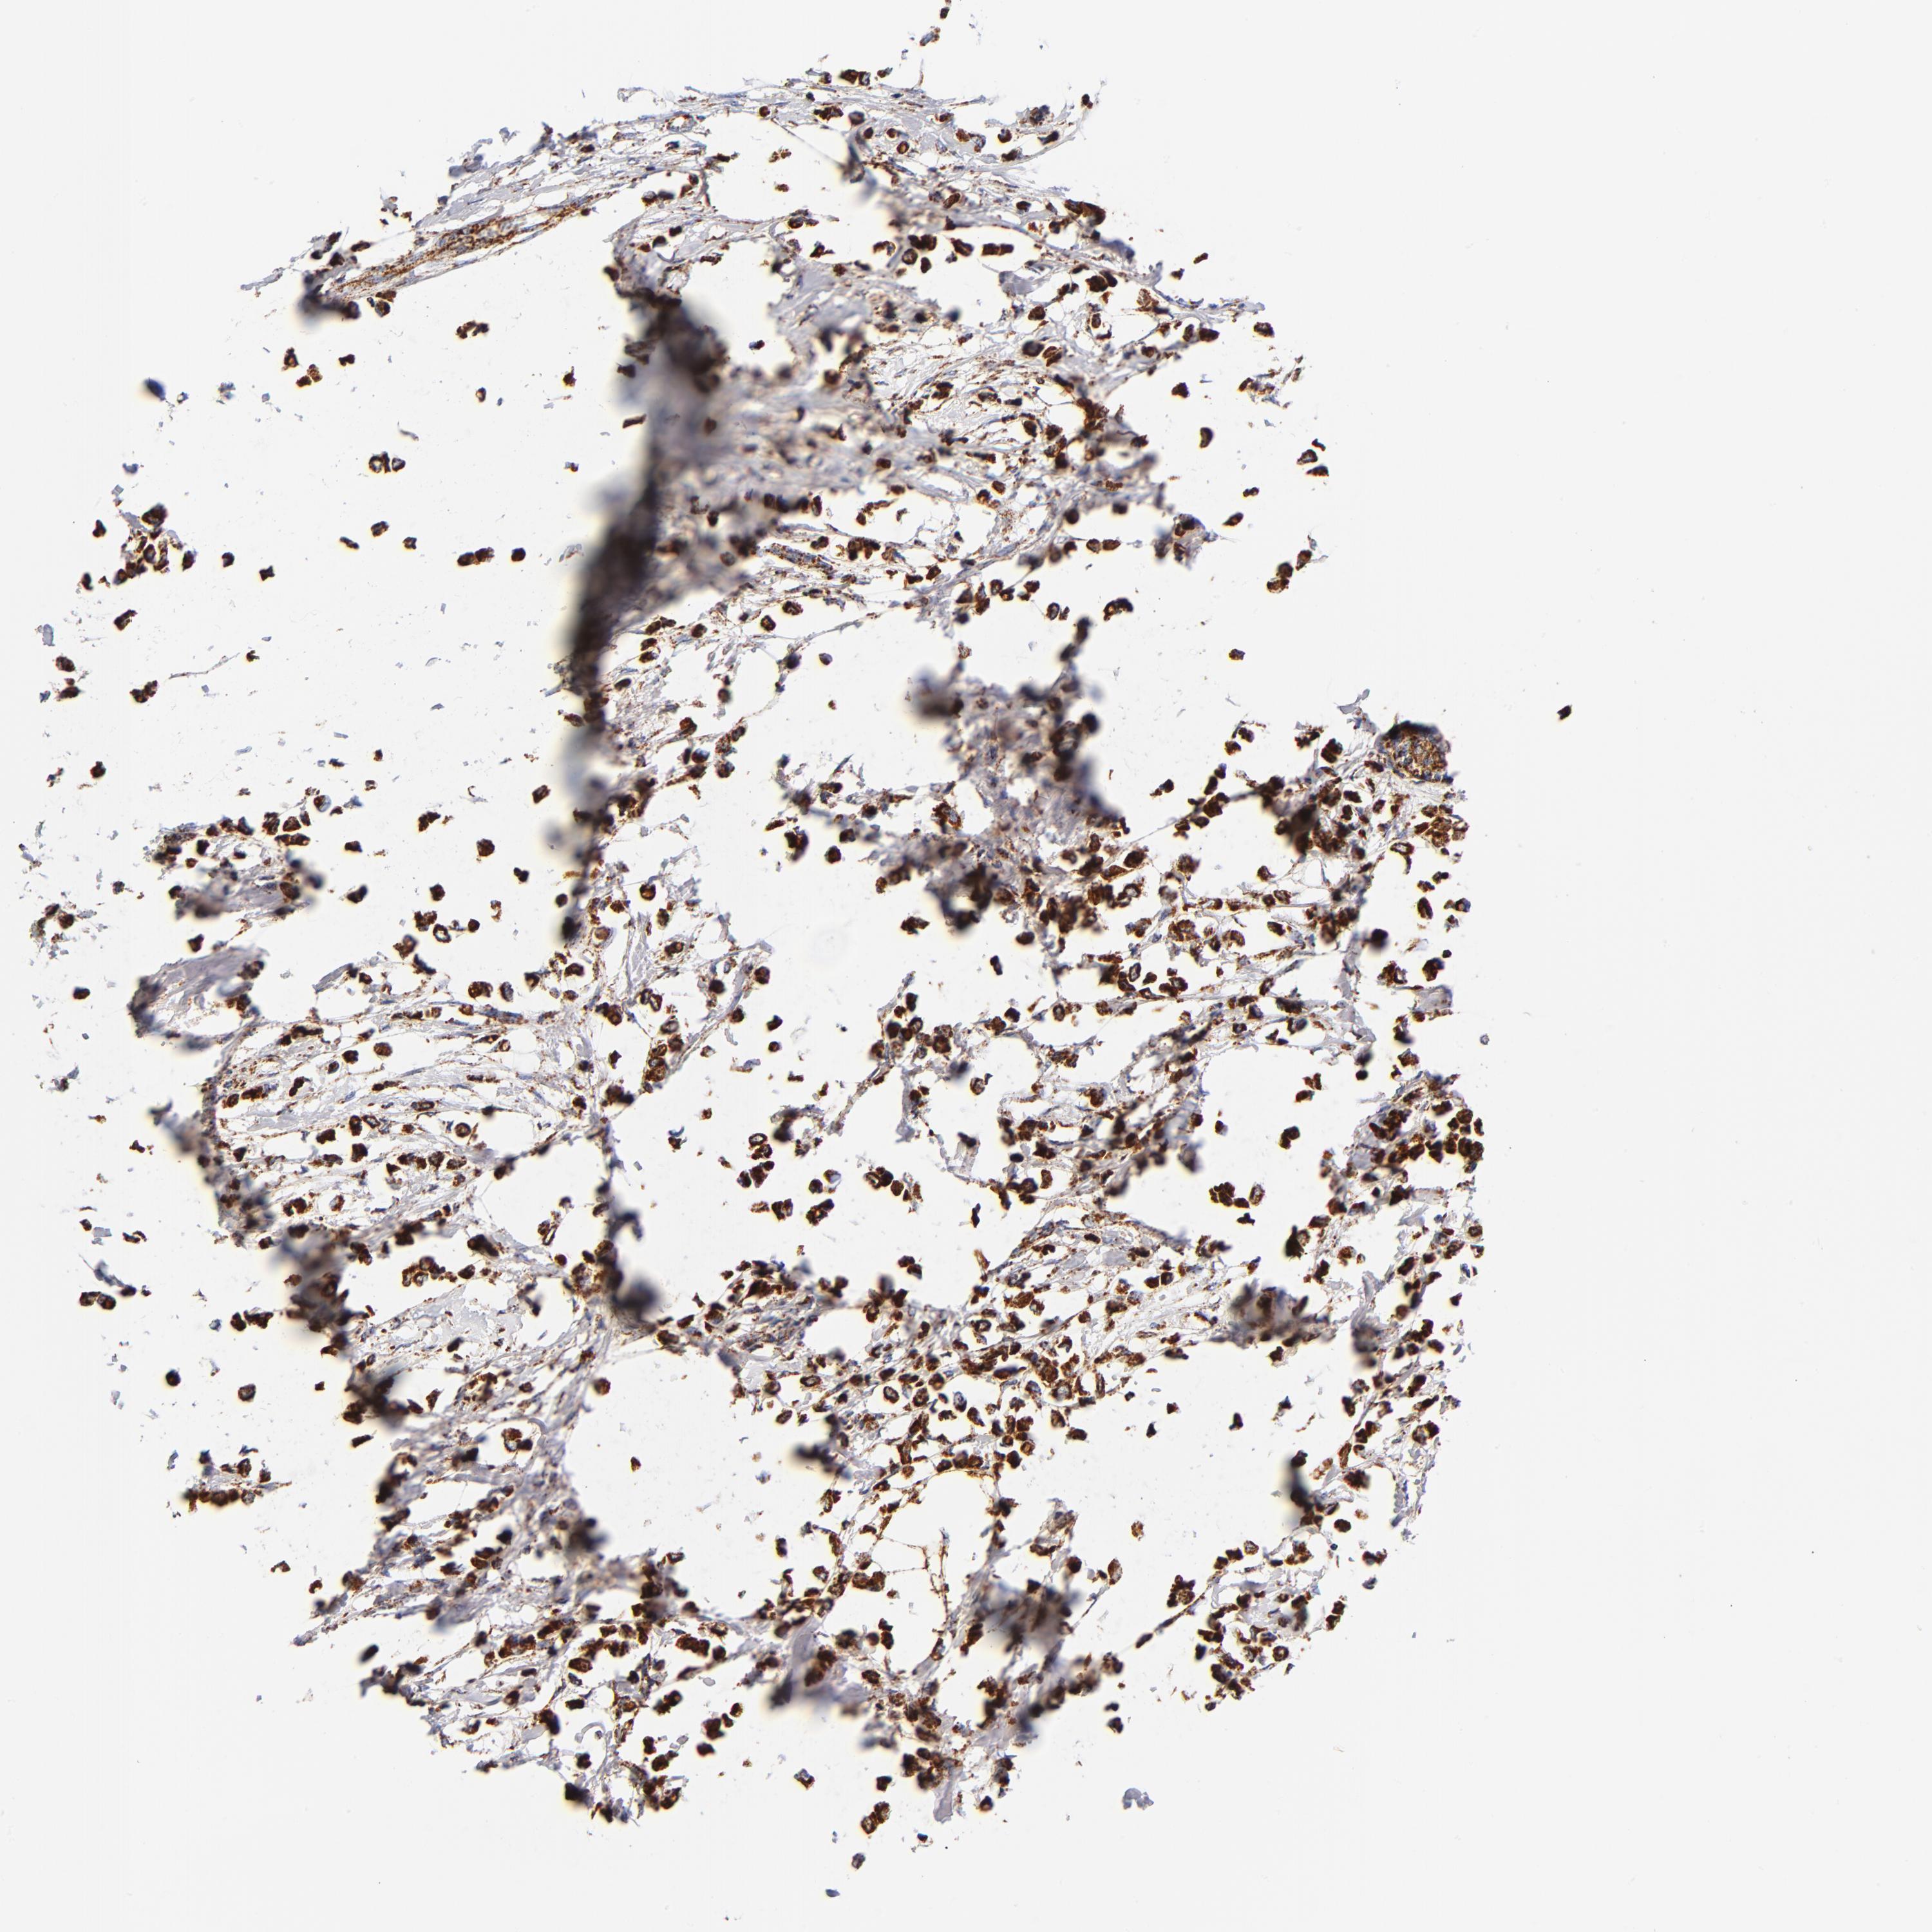

BRCA TCGA BRCA VALIDATION PROTEIN EXPRESSION

Breast cancer

Human cancer

Breast invasive carcinoma